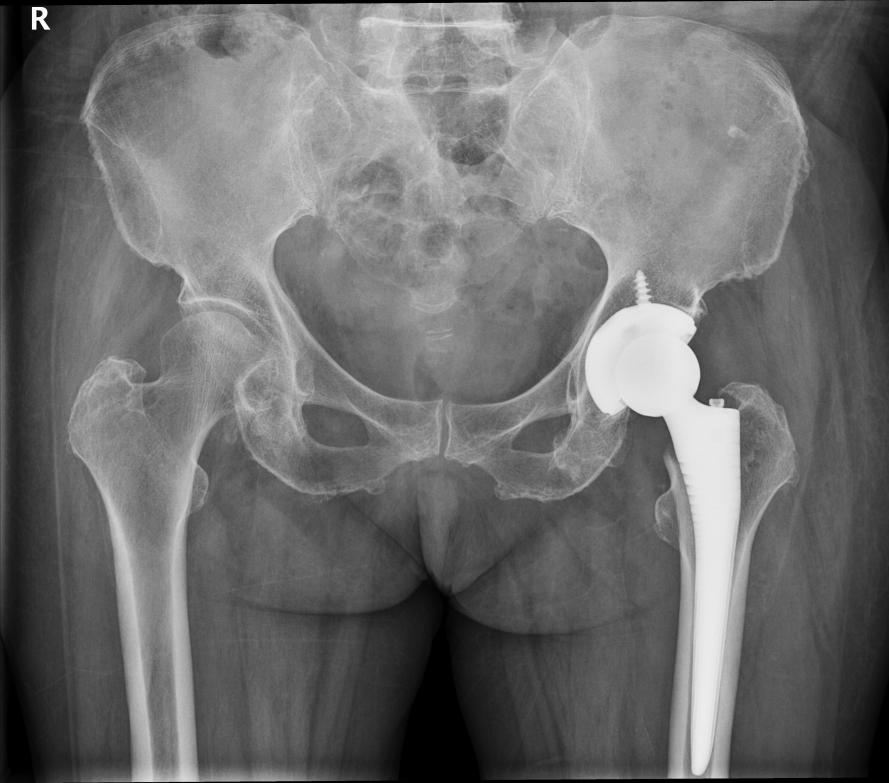

手术团队面临艰难抉择:是保守治疗放弃行走希望,还是冒险手术为生命争取转机?经过多学科会诊,宗金利医生和骨科团队最终决定采用DAA(直接前路入路)全髋关节置换技术——这项微创技术,成为破解困局的唯一“密钥”。

手术当天,手术室里气氛肃穆。宗金利医生和骨科团队穿着手术服,戴着放大眼镜,目光紧盯手术区域。与传统手术不同,DAA技术无需切断任何肌肉,而是从大腿前侧的天然肌间隙进入,如同在“迷宫”中寻找最优路径。

“切口只有8厘米,必须精准避开血管神经,每一步操作都要稳、准、快。”宗金利手持器械,在术中定位系统的辅助下,将人工关节假体精准安放到位。整个手术过程出血控制在200毫升内,远低于传统手术的出血量,最大程度减轻了心脏负荷。麻醉团队同步实施个体化精细化管理,实时监测心率、血压等指标,确保患者循环状态稳定,为手术保驾护航。

3小时40分钟后,手术顺利结束。当缝合最后一针时,手术室里传来轻微的舒气声——这场针对高龄高危患者的微创攻坚战,首战告捷。